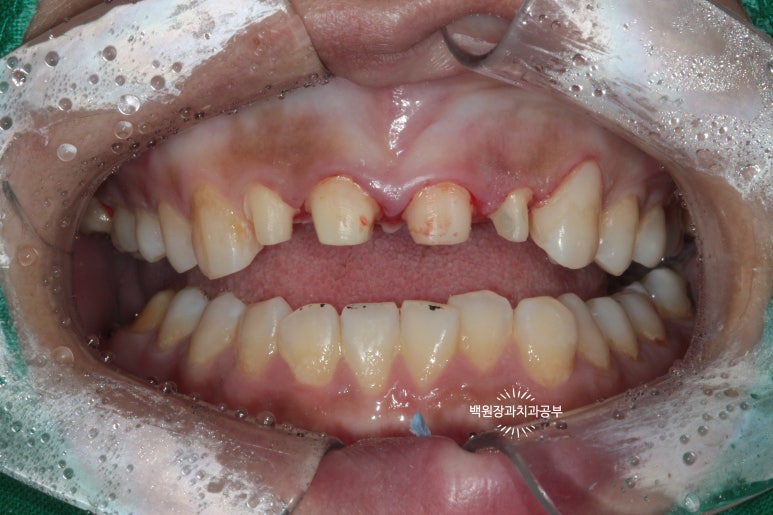

해당 치아의 삭제가 완료되었습니다.!!

치아가 많이 없어져 보여서 속상합니다..

다만 최종 지르코니아 크라운이 최소 2mm 정도의 두께를 얻으려면 이 정도의 삭제는 필수입니다. 더 얇으면 지르코니아 크라운.. 얼마 쓰지 못하고 깨져요!!... 본 환자분의 경우 인접한 면에도 충치가 많이 있었기에 크게 손해보는 상황은 아니었습니다.

위 아래 치아가 교합이 된 상태에서 치아의 삭제량을 다시 한 번 체크합니다.

아주 최소한으로만 삭제가 되었고, 아래 앞니도 조금은 다듬어 주어 지르코니아 크라운의 자리를 확보해줍니다.

좌우로 그리고 앞뒤로 아래턱을 움직여보면서, 크라운이 제작될 공간이 있는지 반드시 확인해야합니다.